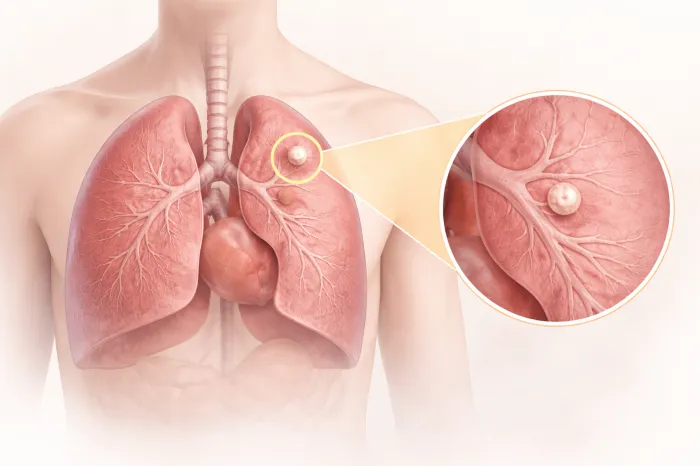

폐결절이란?

폐결절이란 폐 조직 안에 생긴 작은 덩어리를 의미합니다. 보통 흉부 엑스레이나 CT 검사에서 우연히 발견되는 경우가 많으며, 크기는 대개 3cm 이하입니다. 이보다 큰 경우에는 다른 용어로 구분하기도 합니다. 폐결절은 하나만 보일 수도 있고, 여러 개가 동시에 발견되기도 합니다.

중요한 점은 폐결절이 하나 발견되었다고 해서 모두 심각한 질환을 의미하는 것은 아닙니다. 염증이 남은 흔적일 수도 있고, 과거 감염 이후 생긴 변화일 수도 있습니다. 다만, 정확한 판단을 위해서는 크기, 모양, 위치, 변화 속도 등을 종합적으로 살펴봐야 합니다.